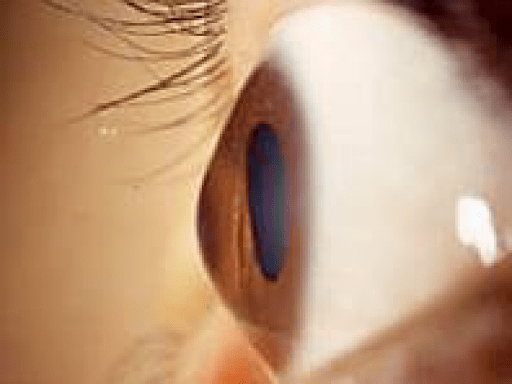

角膜は機能的に、表層と実質、内皮の三層から成り立っています。実質は、主にコラーゲンで構成される比較的硬い組織で、角膜の形を決定する骨格の働きをしています角膜の実質に変性が起こり、角膜がとがってくるのが円錐角膜という病気です。男女比はおよそ3:1で、年齢が増えるにともなって進行します。多くは思春期から青年期(10~20代ぐらい)で診断され、その後進行し、40歳以降になると進行しにくくなる人がほとんどです。しかし、稀に30代以降で発見されて、50歳以降も進行する人もいます。